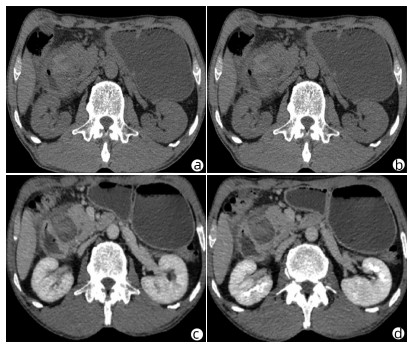

Solitary fibrous tumor of the liver: A case report

Xuecheng LI, Ying FAN, Shuodong WU

2022, 38(3): 632-633. DOI: 10.3969/j.issn.1001-5256.2022.03.026

Abstract(803) HTML (221) PDF (2657KB)(58)

Abstract: